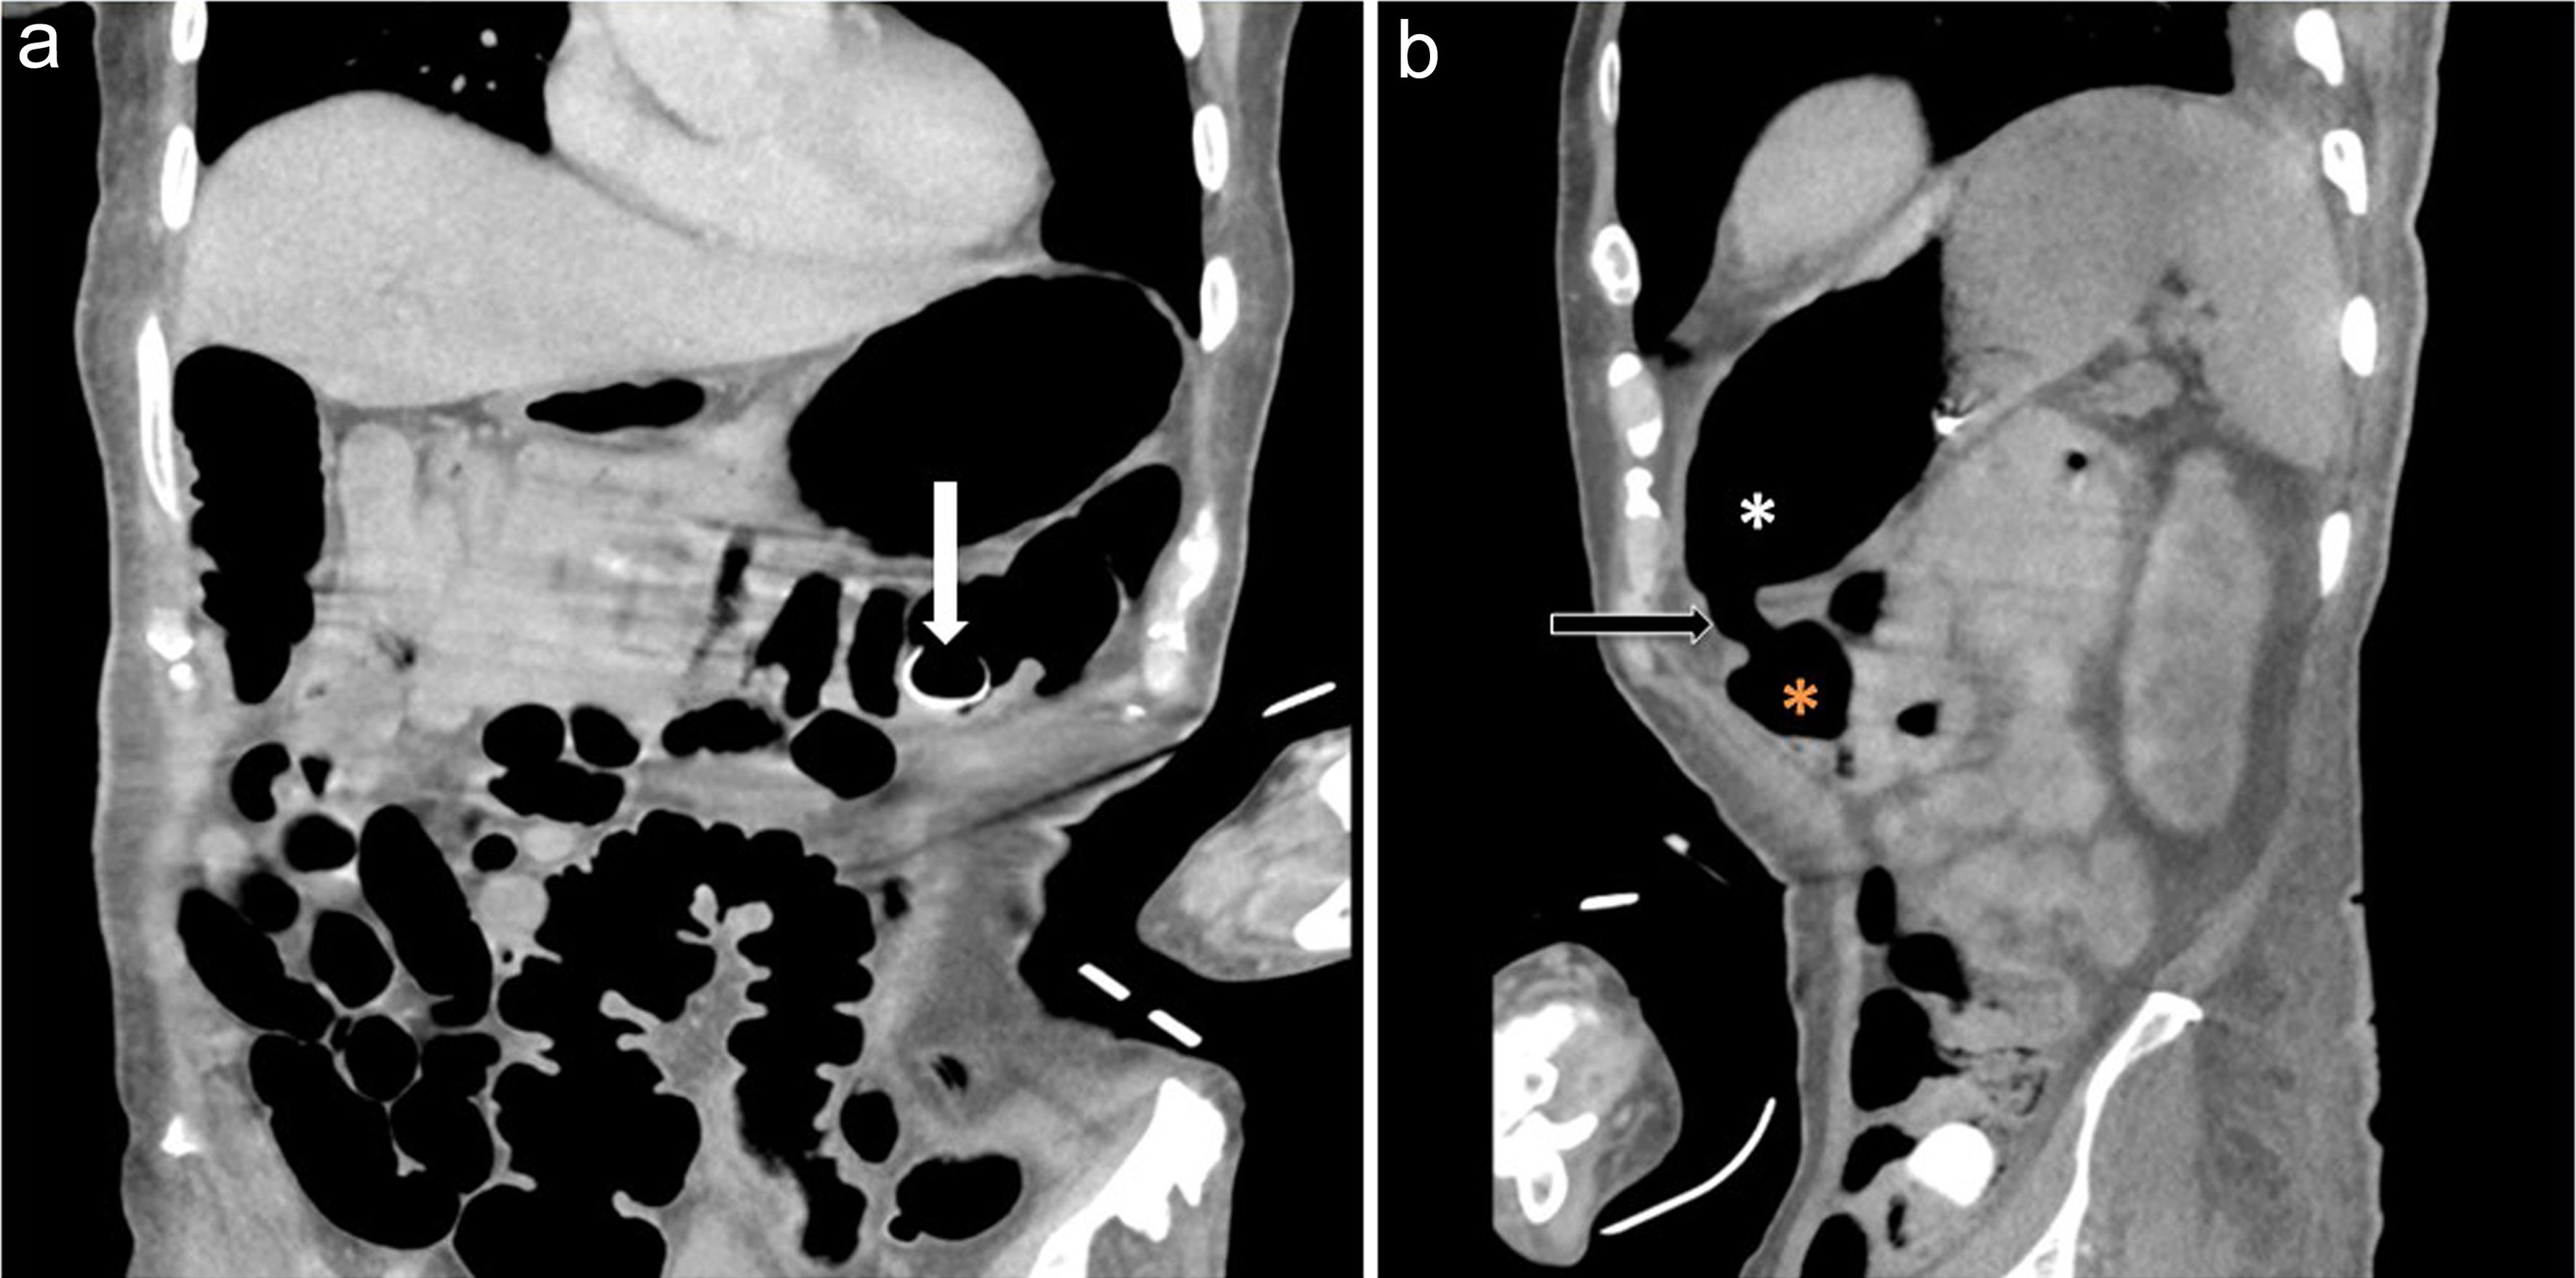

The post-PEG tube placement complication included tube migration and a gastrocolocutaneous fistula. CT imaging confirmed the dislodgement of the gastric balloon bumper from the stomach and its migration into the colonic lumen, as well as the formation of a fistula between the transverse colon and the stomach (Fig. 1a, b).

Coronal (a) and sagittal (b) contrast CT demonstrates the migrated balloon bumper in the distal transverse colon (a, white arrow) and a patent gastrocolic fistula (b, black arrow) between the stomach (white asterisk) and the colon (orange asterisk).

Fig. 1  Coronal (a) and sagittal (b) contrast CT demonstrates the migrated balloon bumper in the distal transverse colon (a, white arrow) and a patent gastrocolic fistula (b, black arrow) between the stomach (white asterisk) and the colon (orange asterisk).